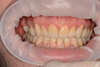

Situation finale